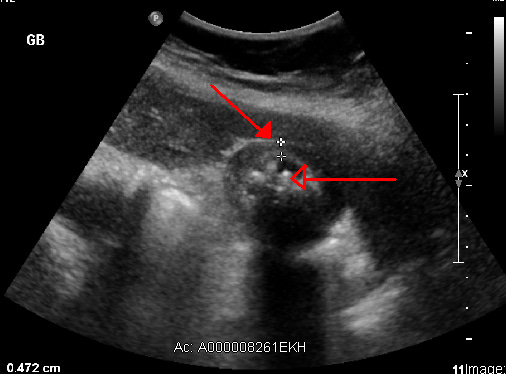

If an ED doc sees cholecystitis on ultrasound, believe them

The diagnosis of cholecystitis can be made quickly and accurately in the emergency department using point-of-care ultrasound, according to a new meta-analysis.